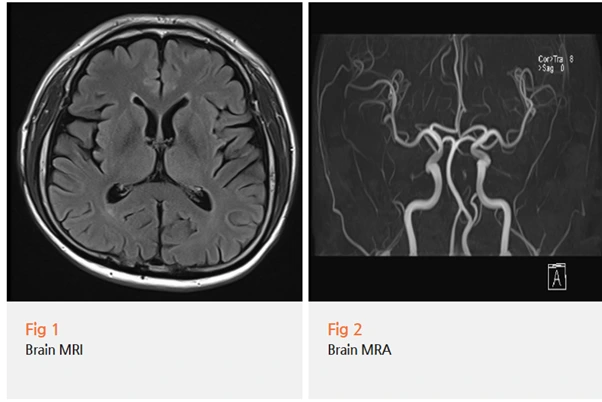

뇌 MRI와 MRA를 시행했는데요.

다행히 뇌 안에는 종양이나 출혈, 혈관 이상 같은

기질적 병변이 전혀 없었어요.

이 결과를 환자분께 말씀드렸을 때, 정말 안도하시더라고요.

그동안 혹시 뇌에 뭐가 있는 건 아닐까 하는 불안감도 있으셨던 거예요.

하지만 뇌가 정상이라고 해서 끝이 아니었어요.

뇌는 괜찮은데 두통은 계속되고 있으니까요.